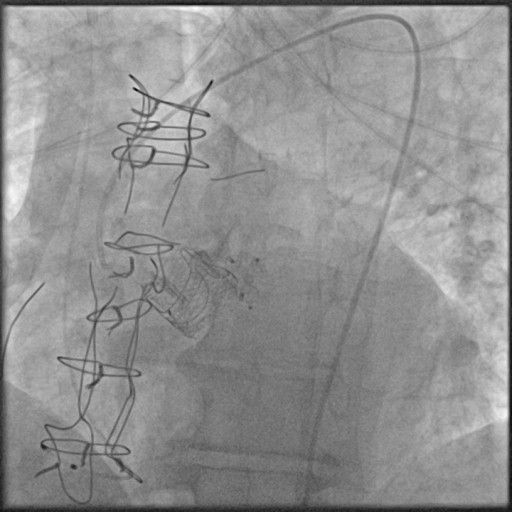

Final result:

Final result showing the absence of any intra-prosthetic or paravalvular regurgitation. Final gradient was 15 mmHg. The patient recently completed 2-year follow-up: he is still asymptomatic with persistently good result at transthoracic echo.